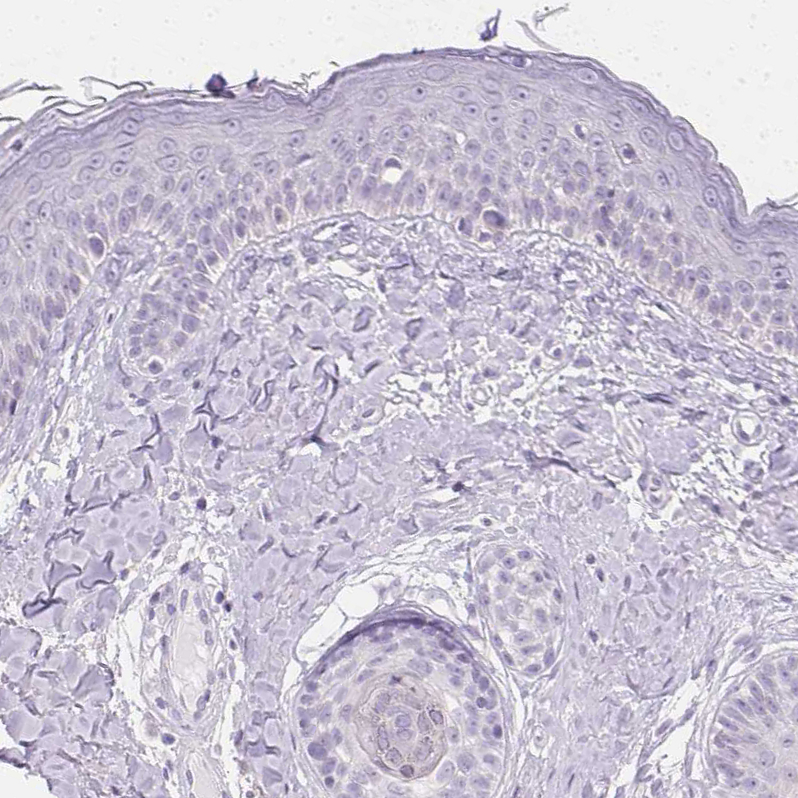

Immunohistochemistry analysis in human kidney and skin tissues using HPA028701 antibody. Corresponding ATP6V1G3 RNA-seq data are presented for the same tissues.